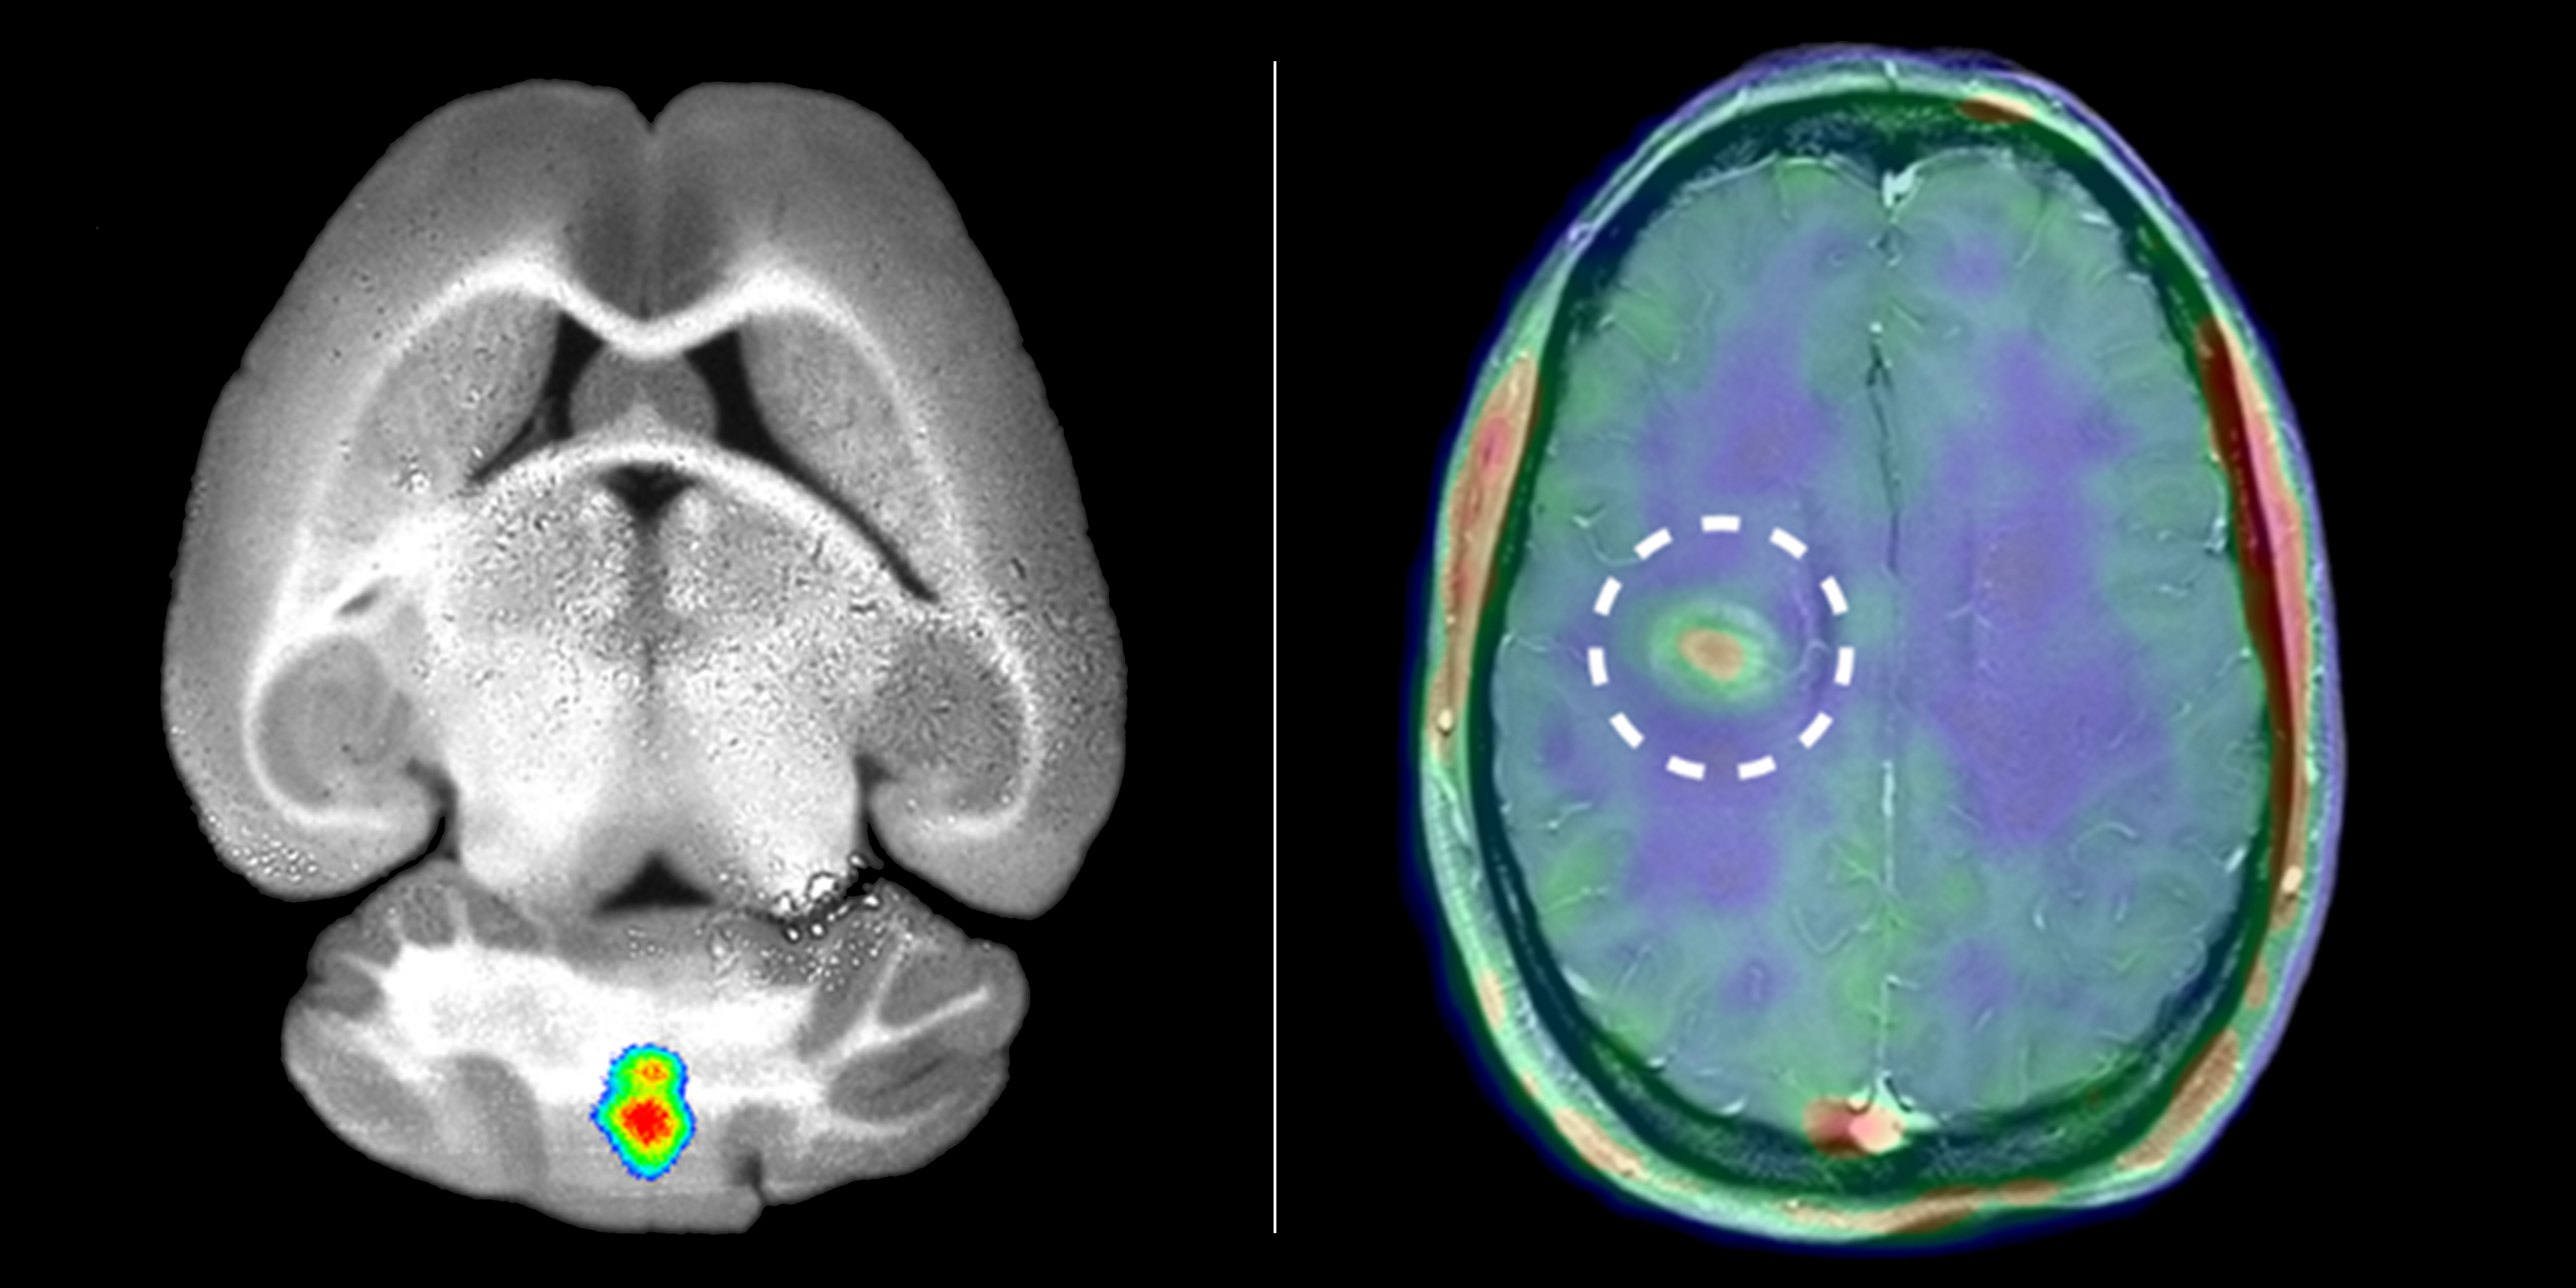

Forscher des Exzellenzclusters "Cells in Motion" machten Entzündungen im Gehirn bei Mäusen (links) und bei Multiple-Sklerose-Patienten (rechts) sichtbar. Dazu markierten sie bestimmte Enzyme (MMPs).

Die CiM-Forscher nutzten erstmals bestimmte Enzyme, die Matrix-Metalloproteinasen (MMPs), um die MS-typischen Entzündungen im Gehirn darzustellen. In einer Vorstudie hatten Biologen und Biochemiker um CiM-Sprecherin Prof. Lydia Sorokin festgestellt, dass diese Enzyme eine entscheidende Rolle spielen. Sie hatten Mäuse mit einer der Multiplen Sklerose ähnlichen Erkrankung untersucht und herausgefunden: MMPs ermöglichen Immunzellen, die Blut-Hirn-Schranke zu überwinden und ins Gehirn zu wandern, wo sie Entzündungen auslösen.

Um die Enzyme im Organismus zu markieren und in Bildern sichtbar zu machen, entwickelten Nuklearmediziner und Chemiker um CiM-Co-Koordinator Prof. Michael Schäfers einen "Spürstoff", im Fachjargon Tracer genannt. Diese chemische Substanz spürt die gesuchten Enzyme im Körper auf und bindet sich an sie. Die Chemiker koppelten einen Fluoreszenz-Farbstoff an den MMP-Tracer, dessen Lichtsignale sich mit optischen Verfahren messen lassen. Über das Tracersignal konnten die Forscher zunächst bei Mäusen auf die Aktivität der Enzyme schließen. "Wir stellten fest, dass die Beobachtung der MMPs präzise Informationen darüber liefert, wo Immunzellen die Blut-Hirn-Schranke durchwandern und wo Entzündungen im Gehirn vorkommen", sagt Molekularmedizinerin Dr. Hanna Gerwien.

In ersten Untersuchungen gelang es den Wissenschaftlern, das Verfahren auf den Menschen zu übertragen. Da die Lichtsignale des fluoreszierenden Tracers die dickeren Gewebeschichten beim Menschen nicht durchdringen können, wandelten die Forscher den Tracer um und hängten statt des Fluoreszenz-Farbstoffs einen radioaktiven Signalgeber an. Dessen Strahlung lässt sich mit einem speziellen Verfahren, der Positronen-Emissions-Tomographie (PET), messen und sichtbar machen. Nuklearmediziner und Neurologen des münsterschen Exzellenzclusters, die gleichzeitig am Universitätsklinikum tätig sind, führten nun erste Fallstudien bei Patienten mit Multipler Sklerose durch. Das Ergebnis: Bei Patienten mit akutem MS-Schub reicherte sich der Tracer deutlich an, und zwar schon bevor im betroffenen Bereich mit dem traditionellen Verfahren der Magnet-Resonanz-Tomographie eine Schädigung der Blut-Hirn-Schranke zu sehen war.